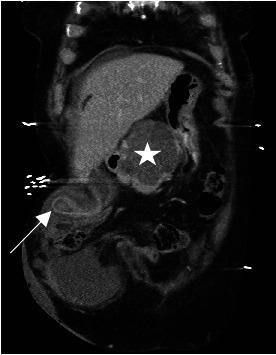

Parastomal hernia is a common complication following an enterostomy. Gallbladder herniation into parastomal hernia is rare and may become symptomatic and inflamed and very rarely can lead to gallbladder perforation. We present the first case of gallbladder perforation inside a parastomal hernia with a unique skin change. . In this report, an 87-year-old female with a history of previous open cystectomy and ileal conduit formation, presented with right upper quadrant pain and worsening parastomal swelling. A computed tomography scan showed a parastomal herniation of the gallbladder, cholelithiasis, and possible early acute cholecystitis. Within 12 hours of admission, bile staining skin changes developed around her urostomy site which raised our suspicion of a perforated gallbladder. Biliary peritonitis was confirmed on laparoscopy the same day. We proceeded with an open midline cholecystectomy without hernia repair. The patient was well at her last follow-up. . A literature review found 14 published cases of incarcerated gallbladder hernia. This uncommon condition mainly affects elderly females. Ten cases were managed operatively, and four cases were managed nonoperatively, with good outcomes. Currently, no consensus on treatment guidelines exists. In a frail elderly patient, a nonoperative approach may be suitable. Operative management was indicated in this case due to clinical concerns of perforation due to developing skin changes. This cutaneous sign has not been previously documented in the literature.

造口旁疝是肠造口术后的常见并发症。胆囊疝入造口旁疝较为罕见,可能出现症状并发生炎症,极少情况下可导致胆囊穿孔。我们报告首例造口旁疝内胆囊穿孔并伴有独特皮肤改变的病例。在本报告中,一名87岁女性,既往有开放性膀胱切除术及回肠代膀胱术史,出现右上腹疼痛及造口旁肿胀加重。计算机断层扫描显示胆囊造口旁疝、胆结石及可能的早期急性胆囊炎。入院后12小时内,其造口周围皮肤出现胆汁染色改变,这引起我们对胆囊穿孔的怀疑。同日腹腔镜检查证实为胆汁性腹膜炎。我们进行了开放性中线胆囊切除术,未行疝修补术。患者最后一次随访时情况良好。文献综述发现14例已发表的嵌顿性胆囊疝病例。这种罕见情况主要影响老年女性。10例接受手术治疗,4例接受非手术治疗,均取得良好效果。目前对于治疗指南尚无共识。对于体弱的老年患者,非手术方法可能合适。由于出现皮肤改变担心穿孔,本病例采用了手术治疗。这种皮肤体征此前文献中未见记载。